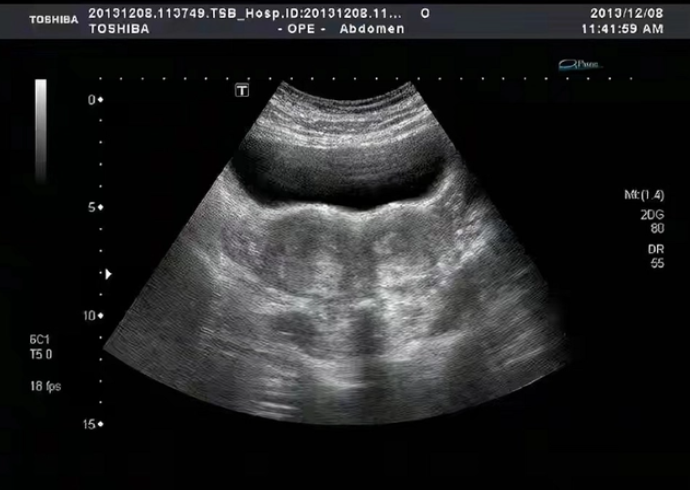

在赵凤琴怀孕的5个月后,赵凤琴隆起的腹部传来了剧烈疼痛,刚开始二人还选择忍受,但是剧烈的疼痛明显出现的很是异常,最终在薛世佳的坚持下,带她去医院里做孕检去了二人又来到了市区医院。赵凤琴开始了检查流程,不查不知道,一查吓一跳!可是医生在给赵凤琴做孕检的时候,竟然发现赵凤芩腹中的孩子不翼而飞了。不管检测医生怎么旋转B超仪器,就是找不到胎儿影像。

现在胎儿的消失,对于夫妻俩来说是当头一棒。他们小心翼翼照顾了整整五个月的胎儿,现在竟然消失不见了?光是这个消息,就险些让夫妻俩晕厥。医生意识到情况不对劲,他们赶紧整召集了专家会诊,又做了几次B超之后,终于看到了胎儿的影像。

医生怀疑赵凤琴是双子宫,她的胎儿隐藏在了另一个子宫里,所以没被发现。而且可以说一般的女子都拥有一个子宫,像这种拥有双子宫的患者更是罕见。但不管怎么样只要孩子是平安无恙的就行了。好在在这是虚惊一场,胎儿还在就还有希望,可是让他们没想到的是,一场巨大的灾难正在眼前等着他们。

而手术室内的医生现在早已经目瞪口呆了,原因是他们将赵凤琴的肚子剖开之后,却没有看到孩子。赵凤琴的子宫内没有胎儿!赵凤琴的子宫里没有影像!主治医师们顿时感到了问题的严重性。医生在左找右找后,终于在她的腹腔找见了一个微弱的胎儿。

医生检查过后发现,赵凤琴此次怀孕竟然是腹腔妊娠,这在全世界仅有1万5千分之一,这种情况极其危险,稍有不慎就是一尸两命。原本该长在子宫里的孩子,竟然在腹腔里存活到如今,也算是一个惊人的生命奇迹。